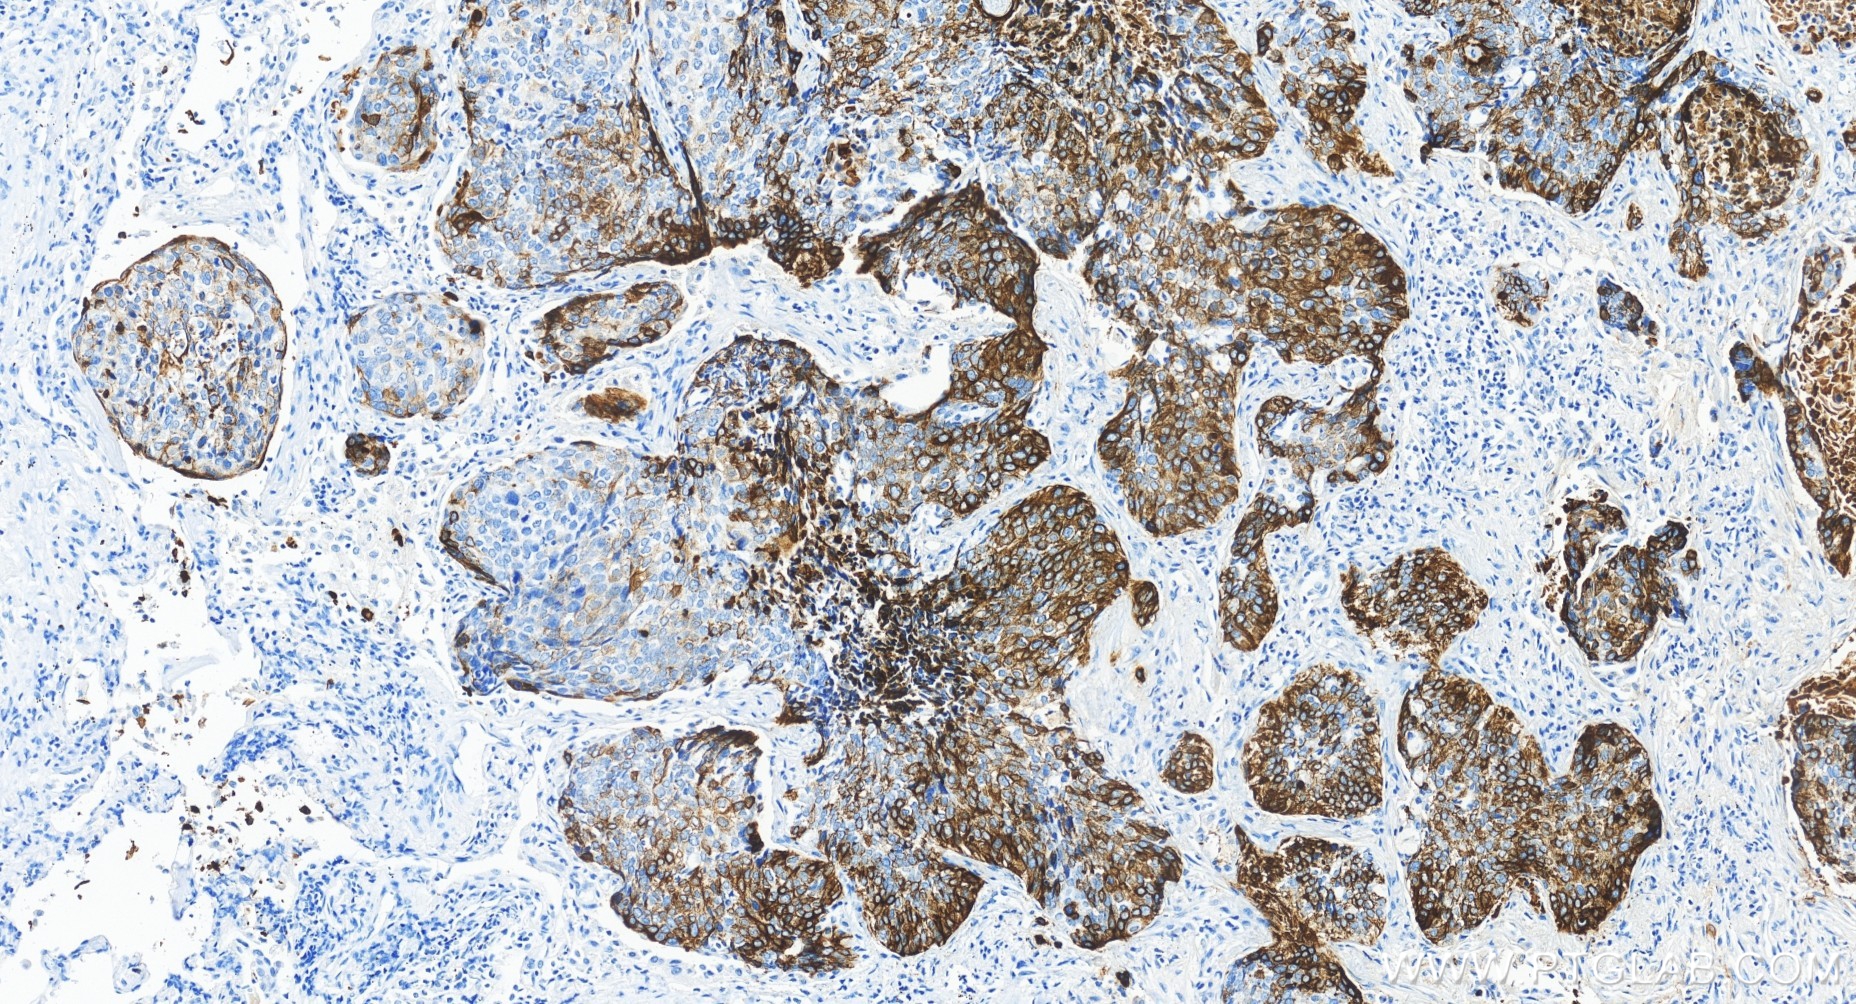

83379-1-PBS targets Cytokeratin 14 in WB, IHC, IF-P, Indirect ELISA applications and shows reactivity with human, mouse, rat samples.

Cytokeratin 14, one of about 20 different cytokeratin isotypes of human cells, is the intermediate filament protein characteristic of epithelial cells. Cytokeratin 14 is expressed in the basal compartment of all stratified squamous epithelia. In various kinds of human tumors, the appearance and increasing expression of Cytokeratin 14 were strikingly associated with higher grade and stage of carcinoma, with varying degrees of unfavorable prognosis. In lung squamous cell carcinoma(LSCC), Cytokeratin 14 was expressed in the tumor cell nests showing stromal invasion with fibrosis and lymph node metastases, indicating that Cytokeratin 14 involved in proliferation and metastasis of LSCC. Cytokeratin 14 expression is sometimes used in diagnosis of myoepithelioma1 and intraductal vs. invasive ductal carcinoma of the breast.